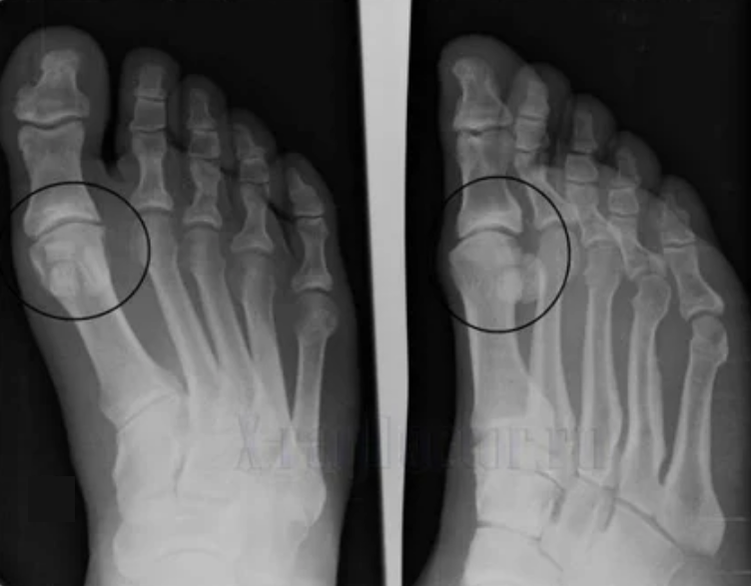

Teşhis yapmak için, romatologlar hastanın şikayetlerini inceler ve bir X -Ray muayenesi öngörürler. Çoğu zaman, radyografi 2 projeksiyonda kullanılır. Doktor, hiyalin kıkırdak ve kemik eklemlerinde distrofik bozuklukların varlığına bakar. Eklem boşluğu azalırsa, kemikler deforme olur veya düzleştirilirse, kıkırdağın yüzeyinde kistik oluşumlar vardır, osteofitler bariz artroz belirtileridir. Muayene sırasında, eklem eklemin kararsızlığını gösterir: uzuvların ekseni ve subluksasyon bozulur.

Genellikle bir x -ray resmi eklemin durumu hakkında tam bilgi veremez. Daha kapsamlı bir çalışma için bilgisayarlı tomografi reçete edilir, kemiklerin incelenmesi için etkilidir. MRG daha sık yumuşak dokuları incelemek için kullanılır.